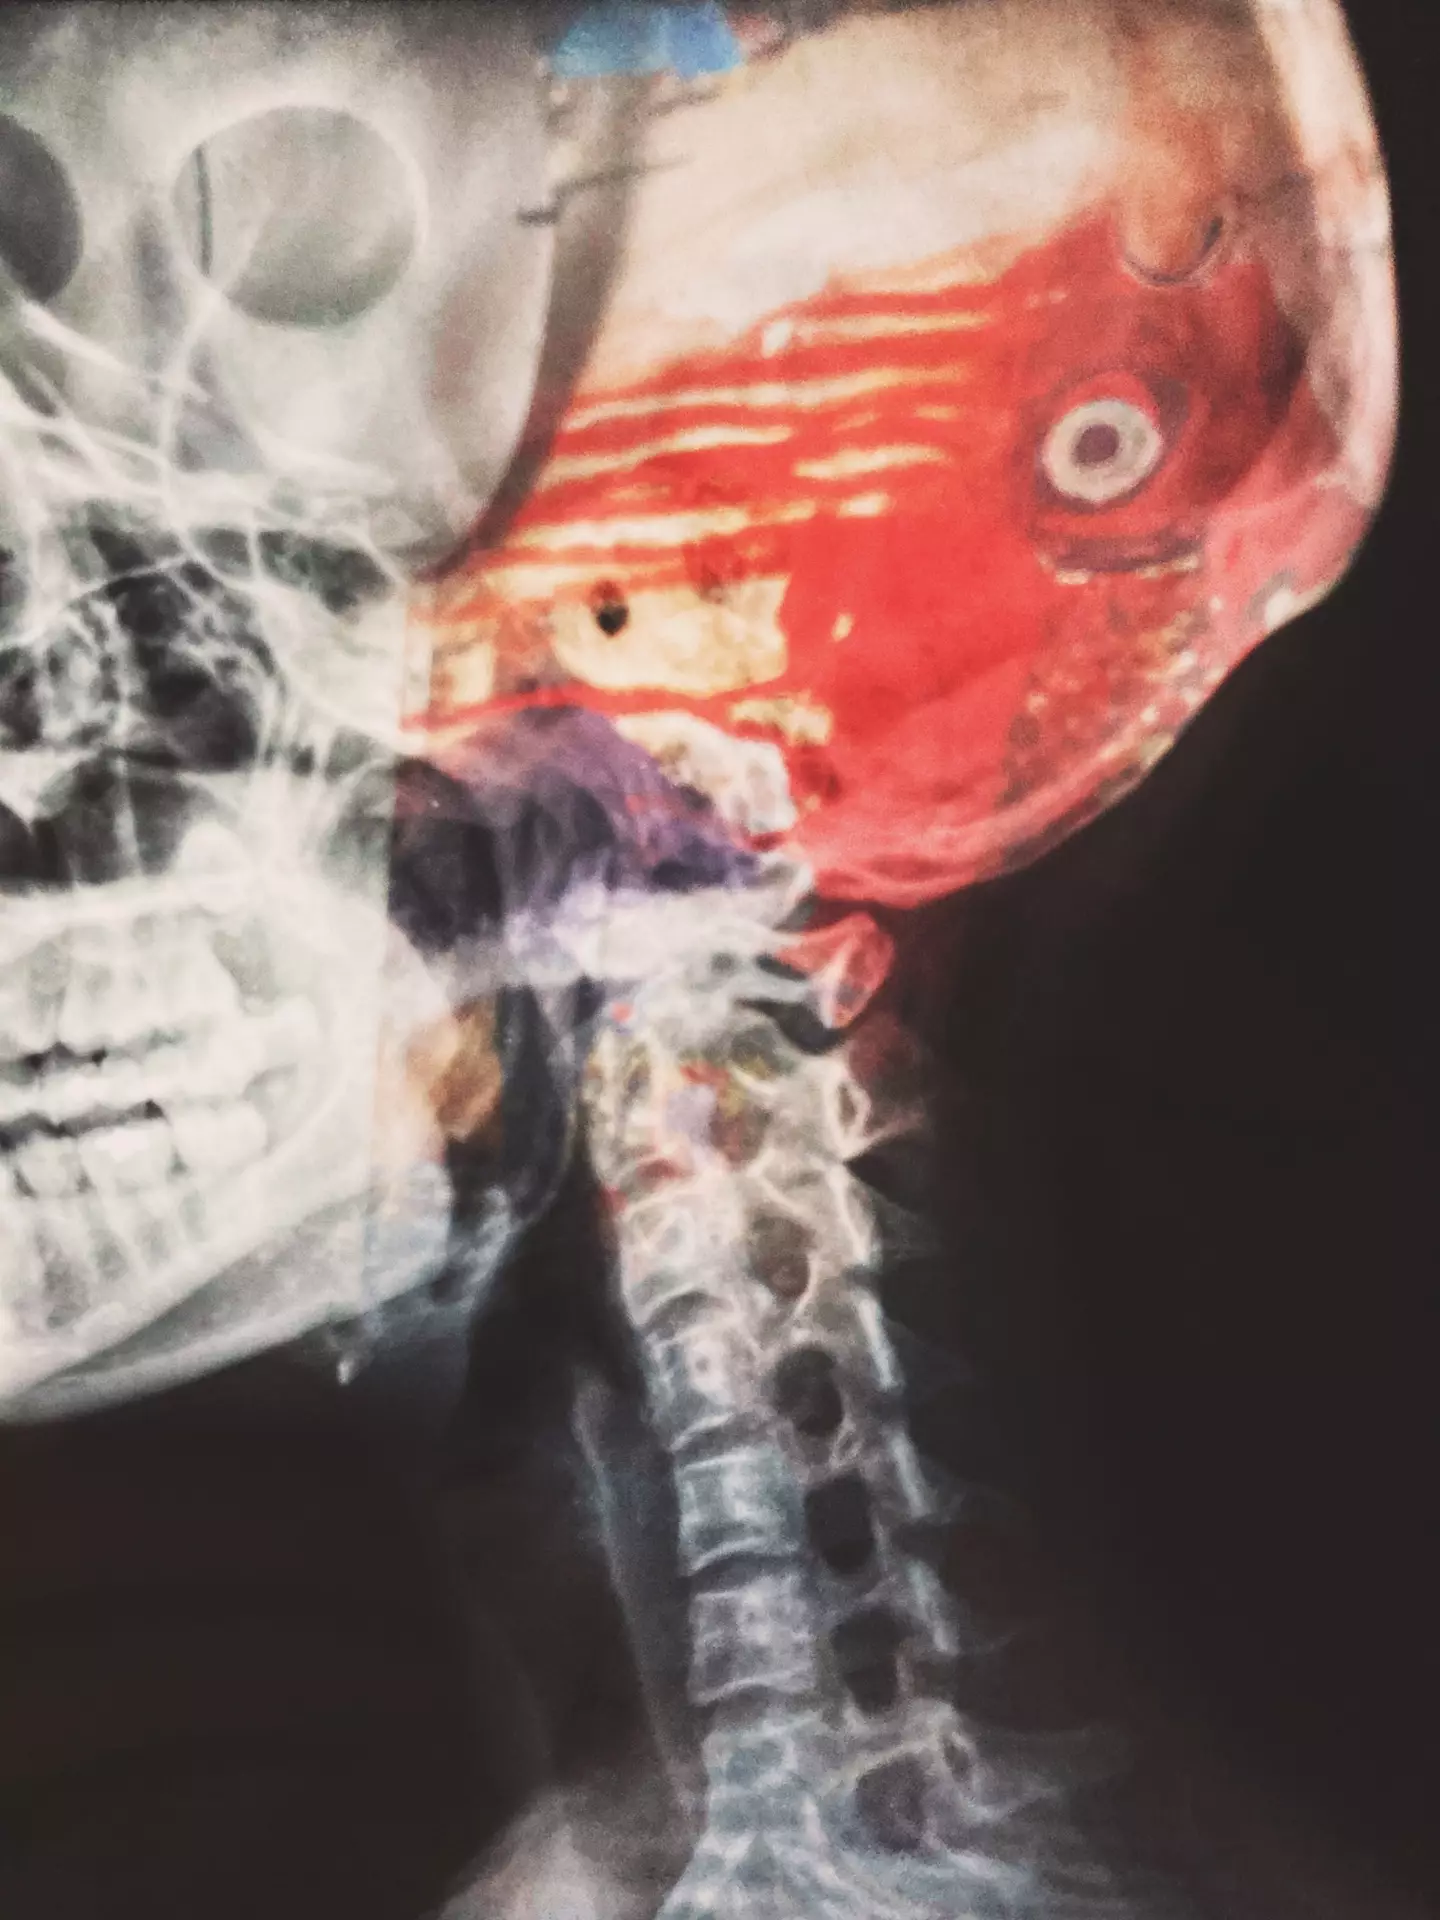

The rare injury - known as internal decapitation - makes up just 1 percent of spinal injuries and sees the skull totally detaching from the spine with the skin still intact.

A sudden impact to the head - like when someone is hit by a car - can cause the ligaments and muscles holding the skull in position to tear.

Hassan was so badly injured, his head was 'almost completely detached from the base of his neck' when he arrived in the emergency room, according to doctors.

The surgery involved fusing the skull and spinal column using rods, screws, plates and, less commonly, bone grafts.